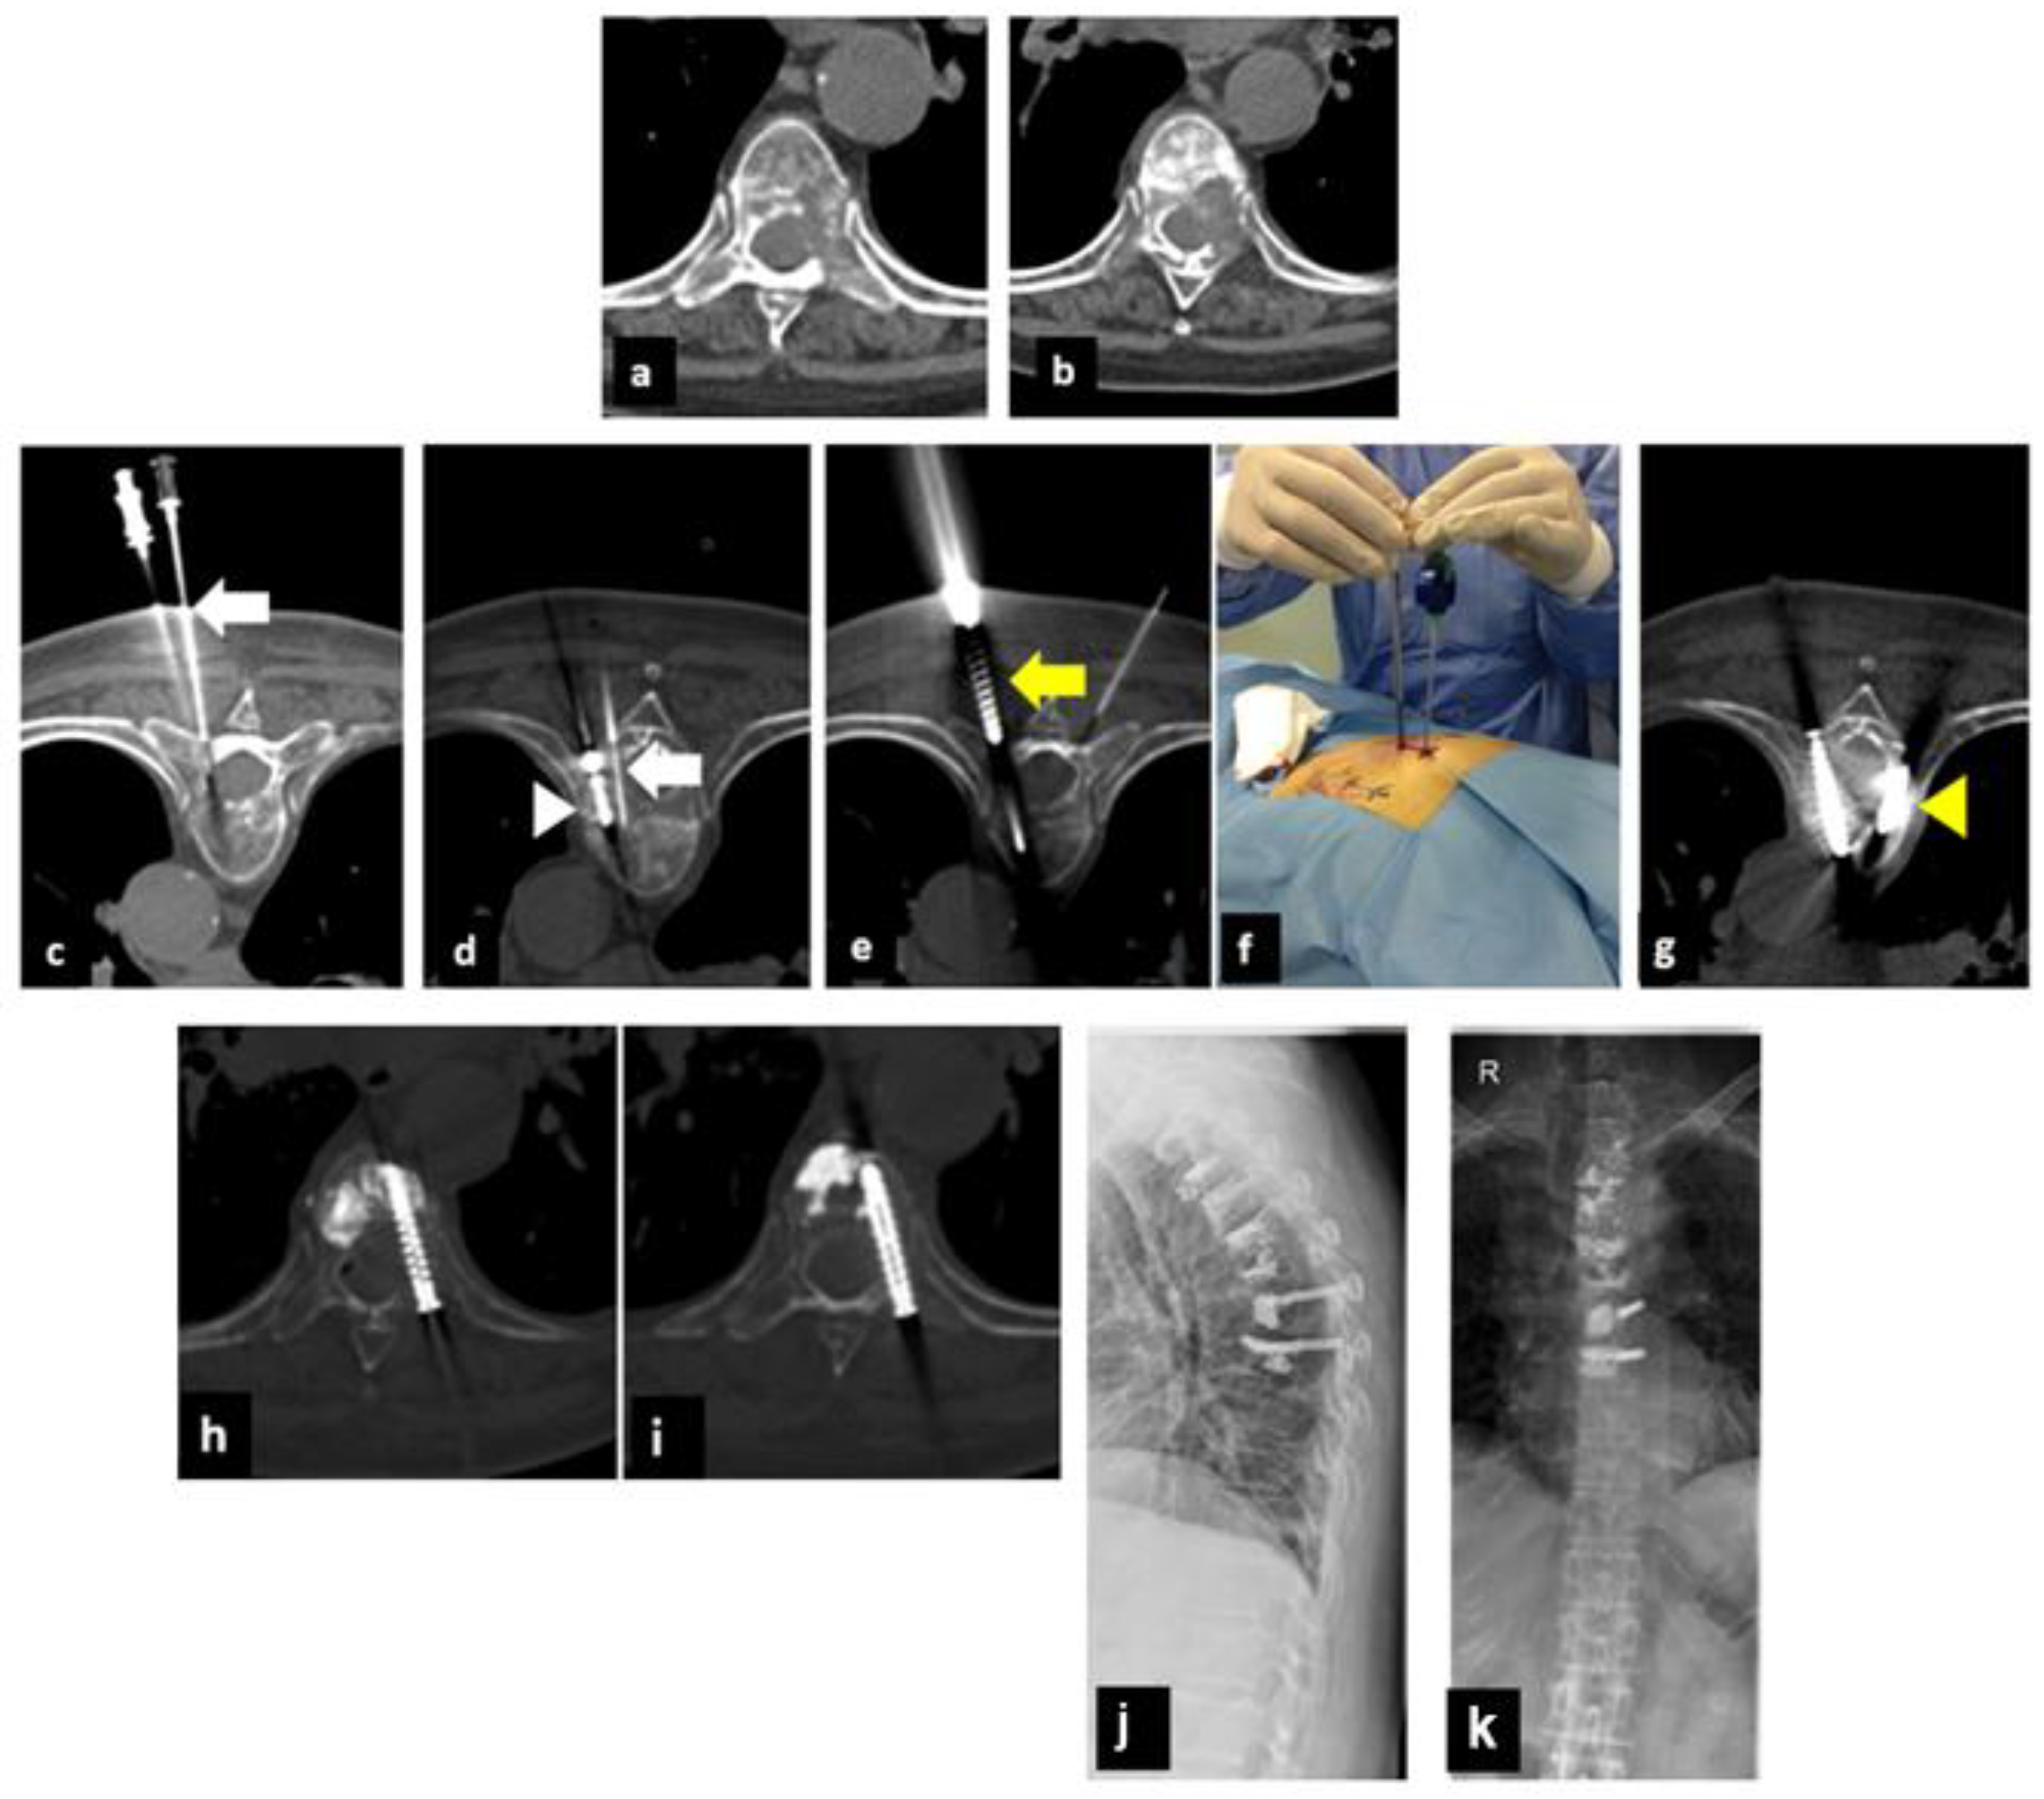

2.1. Treatment Technique